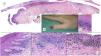

Subungual melanoma. A, Pigmented subungual lesion that generates substantial nail dystrophy, with partial destruction of the nail plate. An evident pigmentation of the exposed bed can be seen, in the hyponychium and the proximal nail fold (Hutchinson sign). B, Low-magnification view of longitudinal nail biopsy (x4), in which an increase in the pigment of the matrix can be seen, as well as sparse foci of accompanying inflammatory infiltrate (arrows). C, Greater detail (x100) of the nail matrix shows a lentiginous proliferation of vacuolated cells (melanocytes), with marked suprabasal ascent; cells thus even become incorporated into the nail plate. This lentiginous proliferation also involves the eponychium. D, At higher magnification (x200), a proliferation of atypical melanocytes can be observed, with suprabasal ascent with invasion of the entire matrix and spread towards the eponychium. E, Detail (x200) of the proximal nail fold. Melanocytic proliferation has now spread to the skin proximal to the eponychium. Once again, a lentiginous proliferation of atypical melanocytes is observed, with presence of atypical cells already in the papillary dermis and accompanying inflammatory infiltrate. Therefore, this melanoma is initially invasive. F, Detail (x200) of the suprabasal ascent of atypical cells, some of which are present in the nail plate. G, Detail (x200) of the nail matrix; ascent to suprabasal layers of atypical melanocytes.

Subungual melanoma. A, Low-magnification longitudinal view of the entire nail apparatus. The patches of inflammatory infiltrate of irregular distribution are already apparent at low magnification of the distal matrix, nail bed, and also in the hyponychium. B, In the clinical image, an irregular and complete melanonychia is shown of the nail of the right thumb. Of note is the punctual pigmentation of the hyponychium (arrow). C, Detail of the matrix with melanocytes with evident atypia (arrow). D, Detail of the hyponychium with proliferation of atypical melanocytes in the basal layer and lymphocyte infiltrate at the base of the epidermal ridge. E, Detail of a nail bed with patchy lymphocyte infiltrate beneath a basal epidermal layer with increased number of melanocytes. F, Detail of the nail matrix with proliferation of atypical melanocytes that are present throughout the full thickness of the nail epithelium.